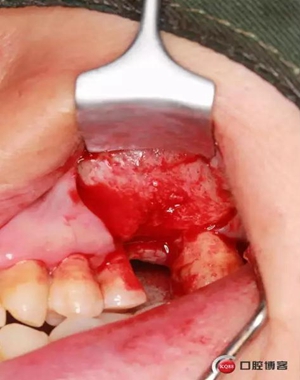

改良式外提升工具盒-外提 科貿(mào)嘉友收錄

大家好,我是梁老師的助理小依。由于梁老師每天手術(shù)檔期安排較滿,加上經(jīng)常出差講課,沒有時(shí)間整理病例 。為了方便大家更及時(shí)的了解梁老師最新手術(shù)動(dòng)態(tài),以后將由我為大家整理并推送梁老師最新經(jīng)典案例。案例文字旁白少,但圖片會(huì)盡量完整展示手術(shù)全過程,供大家學(xué)習(xí)參考。有任何問題,可以留言,梁老師會(huì)親自為大家解答。感謝大家對梁老師的支持和關(guān)注!